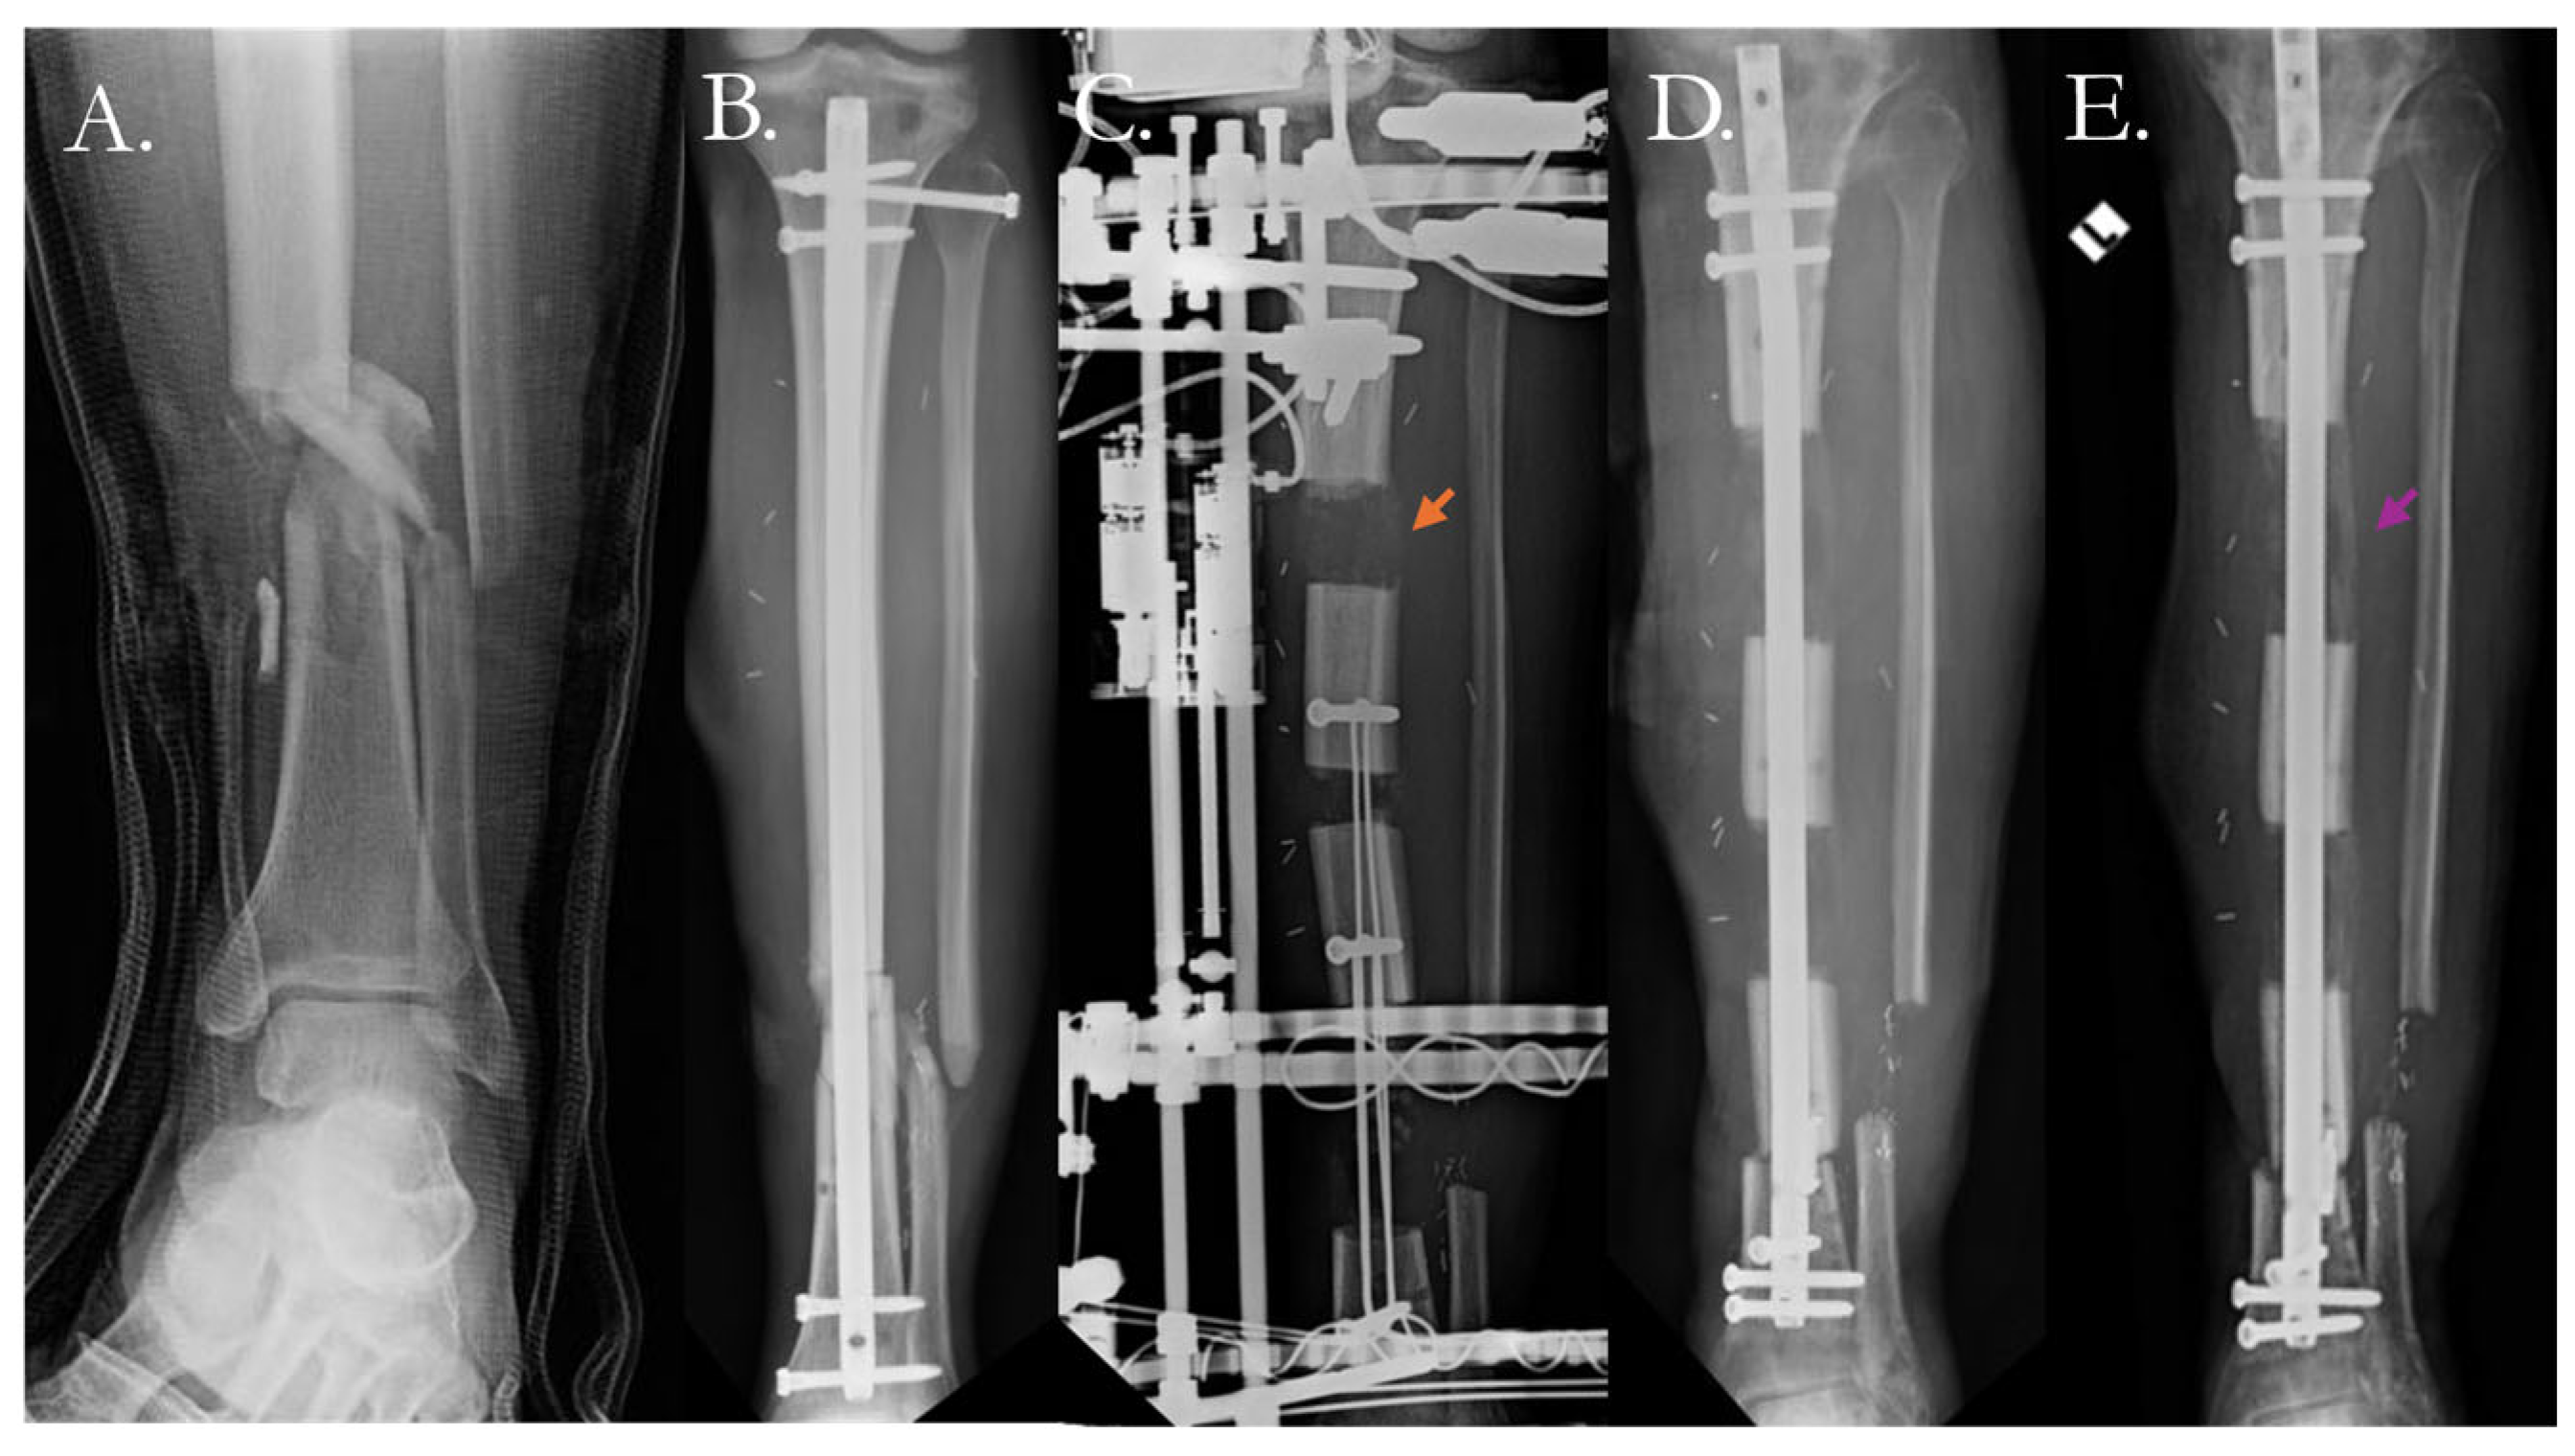

4.2.1. Traditional Surgical Approaches

- Rouse, B.J.; Sheridan, G.A.; Page, B.J.; Fragomen, A.T.; Rozbruch, S.R. Hypertrophic Nonunion Management with Distraction Osteogenesis: A Scoping Review of the Literature. OTA Int. 2024, 7, e342. [Google Scholar] [CrossRef]

- Fragomen, A.T.; Wellman, D.; Rozbruch, S.R. The PRECICE Magnetic IM Compression Nail for Long Bone Nonunions: A Preliminary Report. Arch. Orthop. Trauma. Surg. 2019, 139, 1551–1560. [Google Scholar] [CrossRef] [PubMed]